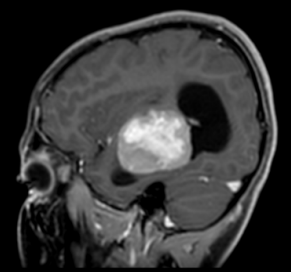

👧A 14-year-old girl presents with progressive right-sided hemiparesis over 4 months. No fever, weight loss, or lymphadenopathy. Exam: mild dysphasia, right hemiparesis, Babinski positive. 👨‍⚕️What would be your differential?

👧A 14-year-old girl presents with progressive right-sided hemiparesis over 4 months. No fever, weight loss, or lymphadenopathy. Exam: mild dysphasia, right hemiparesis, Babinski positive.

👨‍⚕️What would be your differential?